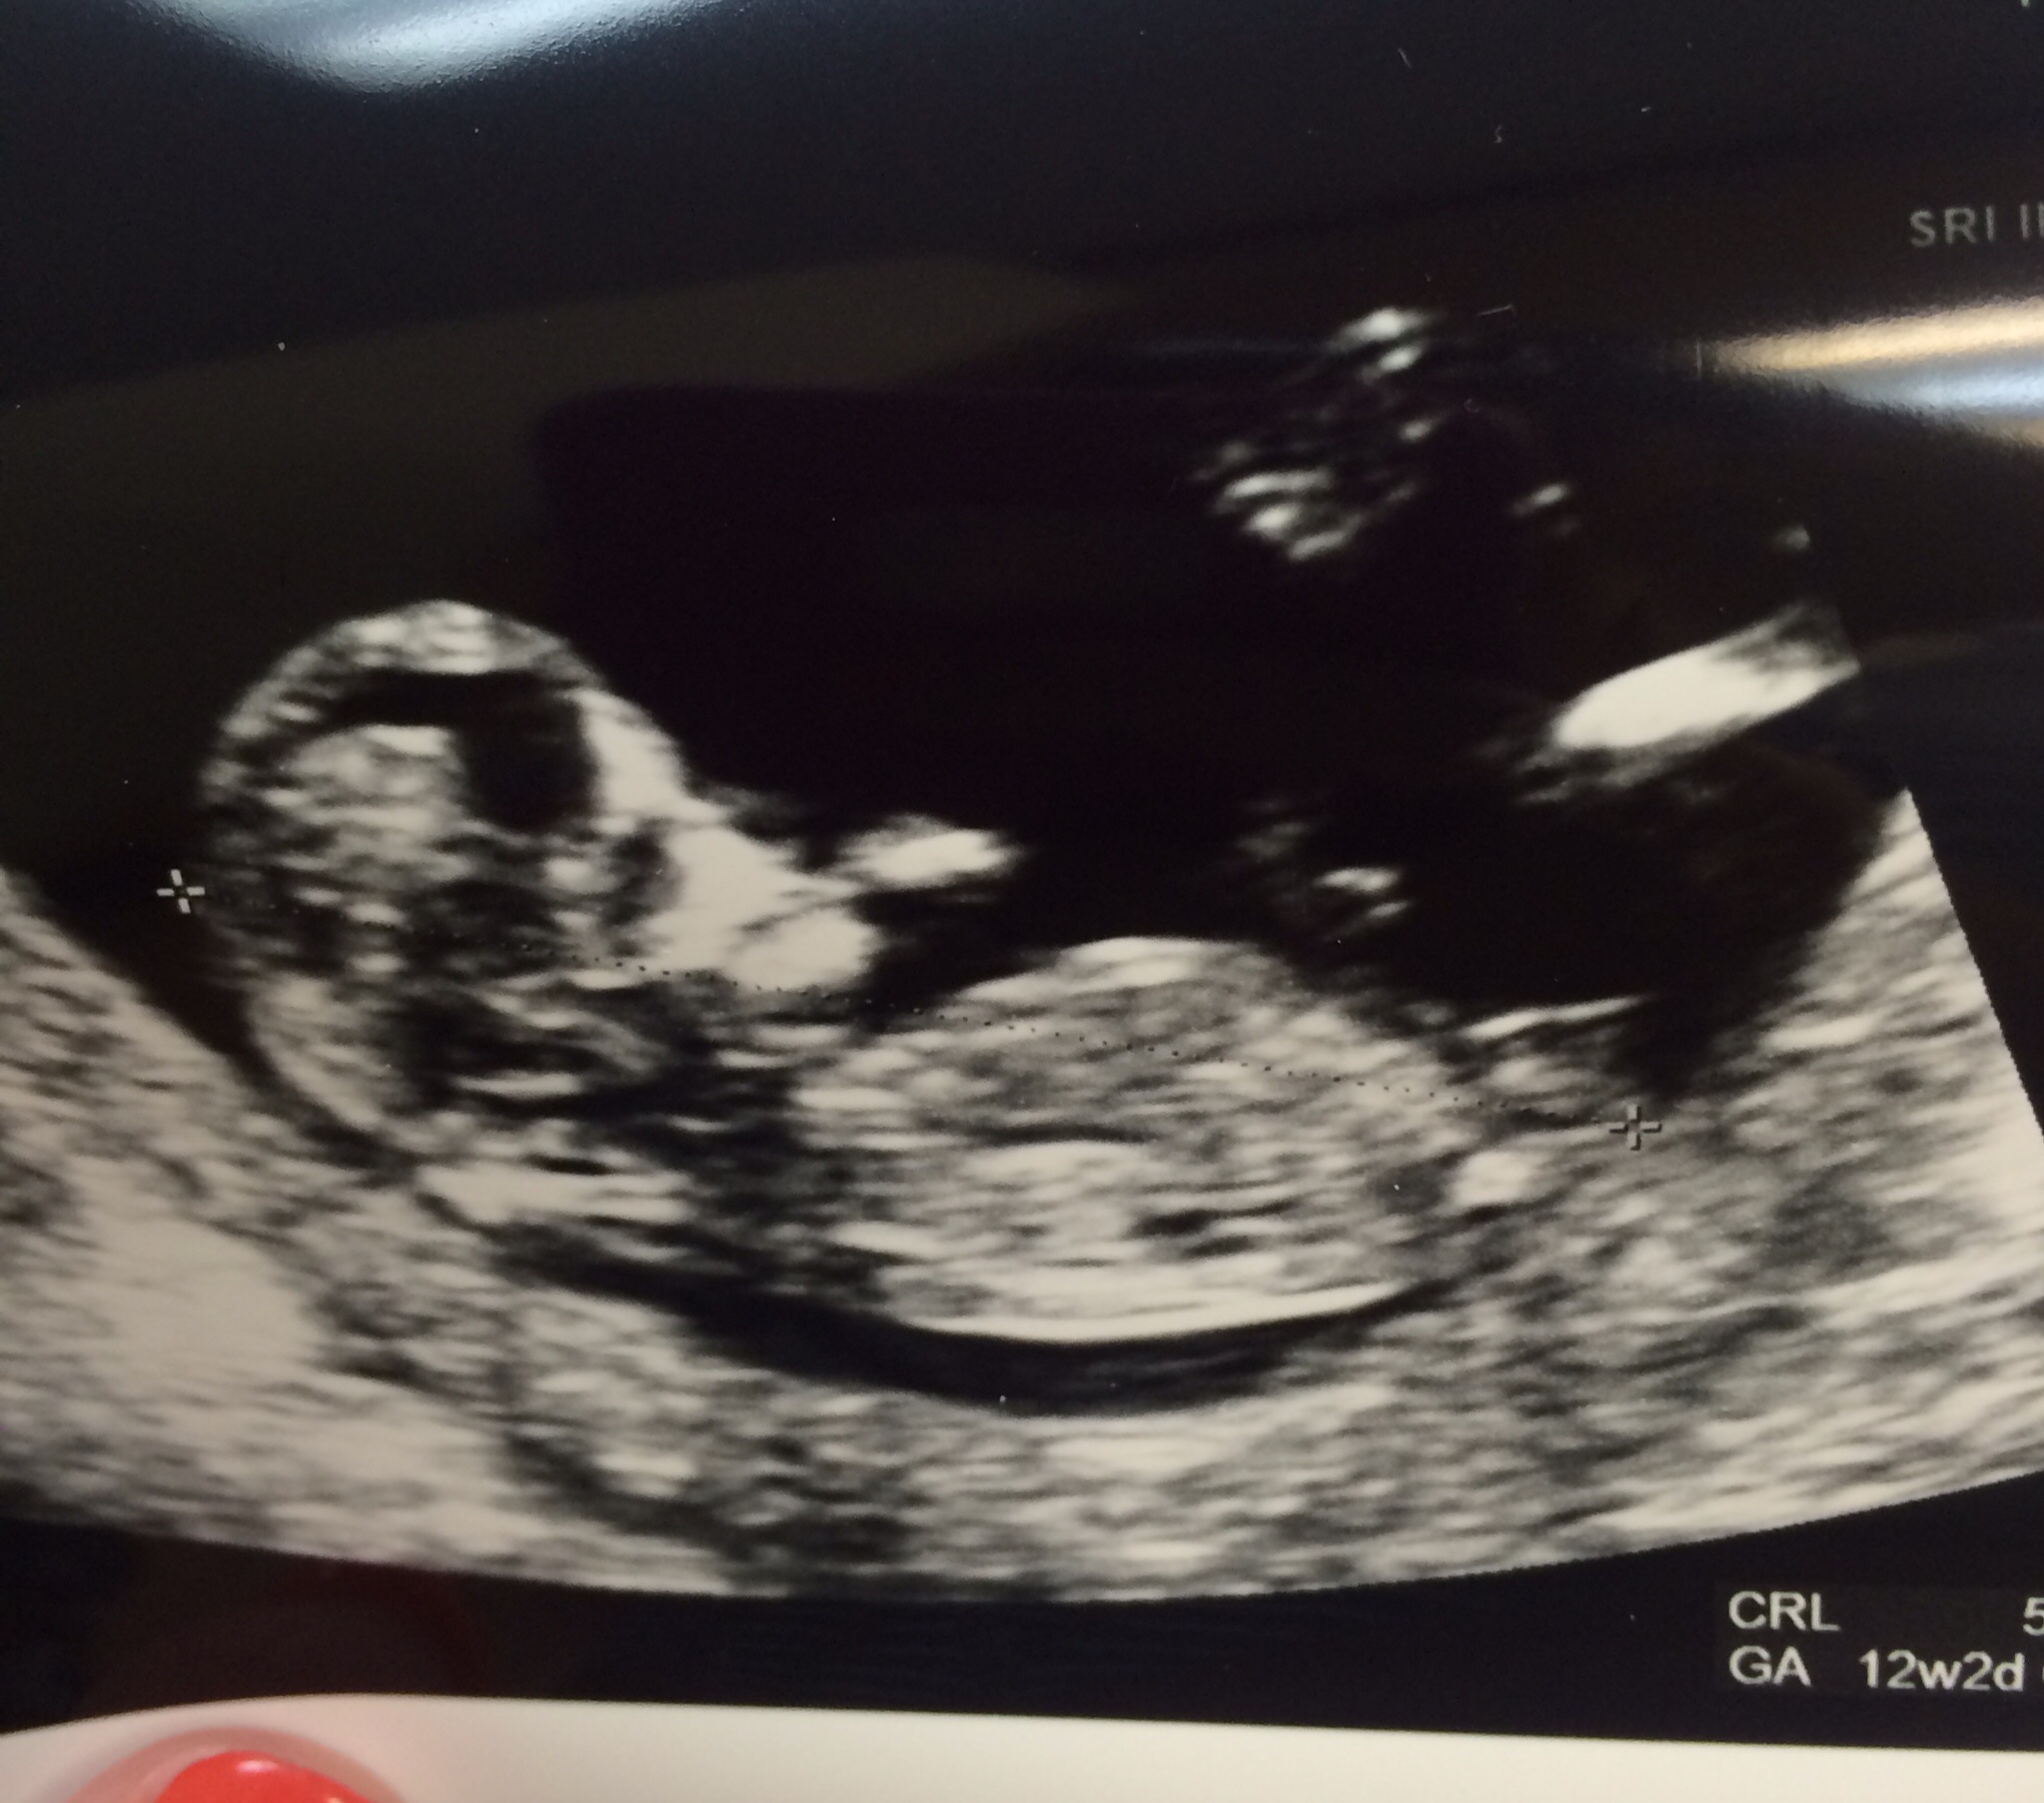

Please guess for me- PsIP of NT scan :)